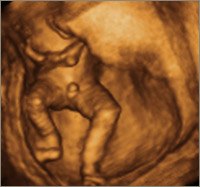

De første 3 billeder er alle uge 15. De to første er dreng og det sidste pige. Det sidste billede er også en pige... Kan derfor godt forstå at hun ikke er helt sikker på kønnet... men tror alligevel jeg tænker dreng

Vedhæftede fotos (klik for at se i fuld størrelse)

Jeg synes jeg kan se en sammenligning mellem dit nummer 2 billede og mit nummer 4 billede (som er en pige) og ellers så synes jeg at jeres ligner mest en dreng...